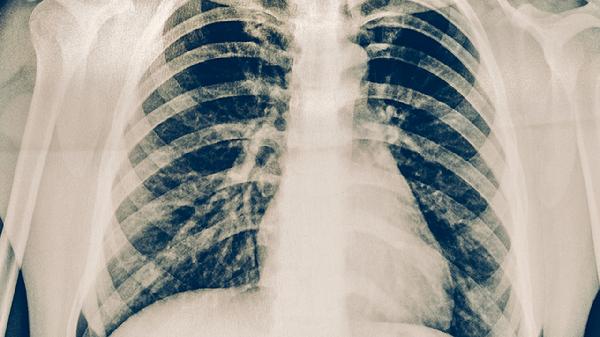

完成療程后仍需定期進(jìn)行胸部X線或CT檢查、痰涂片培養(yǎng)等監(jiān)測。建議治愈后前2年每3-6個(gè)月復(fù)查一次,后期每年隨訪。若出現(xiàn)咳嗽咳痰加重、低熱盜汗等癥狀需立即就診,早期發(fā)現(xiàn)復(fù)發(fā)跡象可及時(shí)干預(yù)。